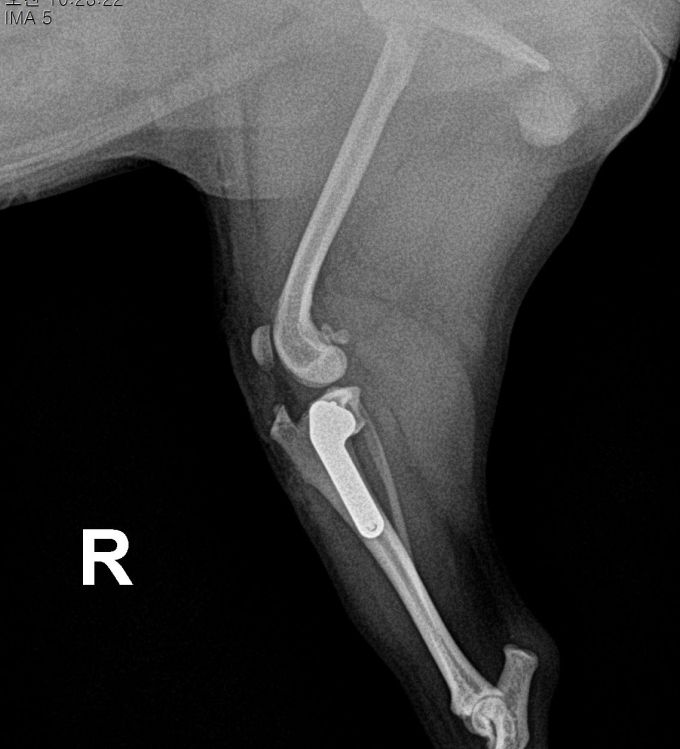

AFTER